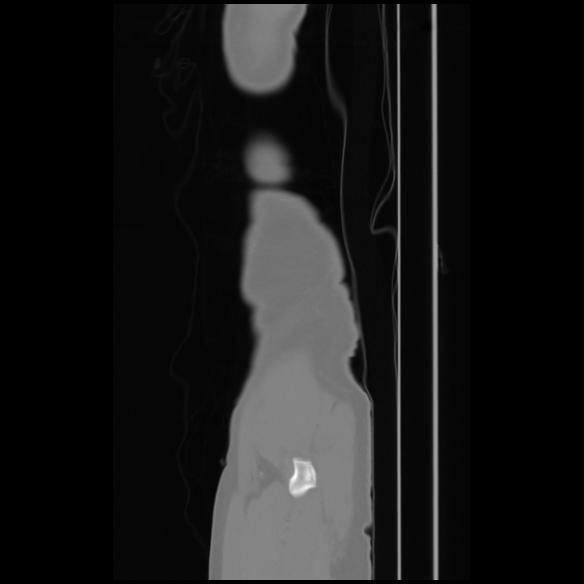

7 CUERPO,CE,Sagittal,3.000,CUERPO,Sagittal,